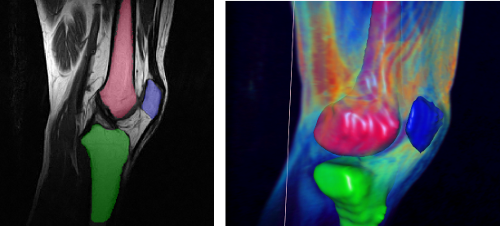

Ziel dieser Arbeit ist es, unter Verwendung des am Welfenlab entwickelte YaDiV Deformable Model Framework (YDMF) angepasste Modelle für die knöchernen Strukturen im Bereich des menschlichen Kniegelenks (Patella, Femur, Tibia) zu entwickeln. Als Volumendaten werden MRT-Aufnahmen zum Einsatz kommen, was eine zusätzliche Herausforderung an das Modell darstellt, da die Differenzierung von knöchernen Strukturen durch Weichgewebe in MRT-Aufnahmen erschwert wird.

Als erster Schritt soll ein Modell für die Patella entwickelt werden, welches mit anatomischen Landmarken versehen wird und durch eine lokal und global angepassten Expansions- bzw. Erosionskraft die Strukturfindung ermöglicht. Das Modell soll mit einer geringen Auswahl an Datensätzten trainiert und anschließend durch die Anwendung in neuen Aufnahmen evaluiert werden. Die gewonnen Erkenntnisse sollen dann für die Modellierung der Femur bzw. Tibia Modelle genutzt werden, bei denen die zusätzliche Herausforderung besteht, das hier oft nur eine Teilabdeckung im Aufnahmebereich besteht.